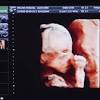

Frozen Embryos Tied to Higher Live Birth Rates in PCOS Women with polycystic ovarian syndrome (PCOS) may have greater success with in vitro fertilization (IVF), in terms of live birth rates, with frozen rather than fresh embryo transfer, according to results published in the August 11 issue of the New ...

Frozen embryos might lead to better IVF success Most women who do IVF are impregnated with a fresh embryo. However, a new study suggests using a previously frozen and then thawed embryo may have a better success rate.